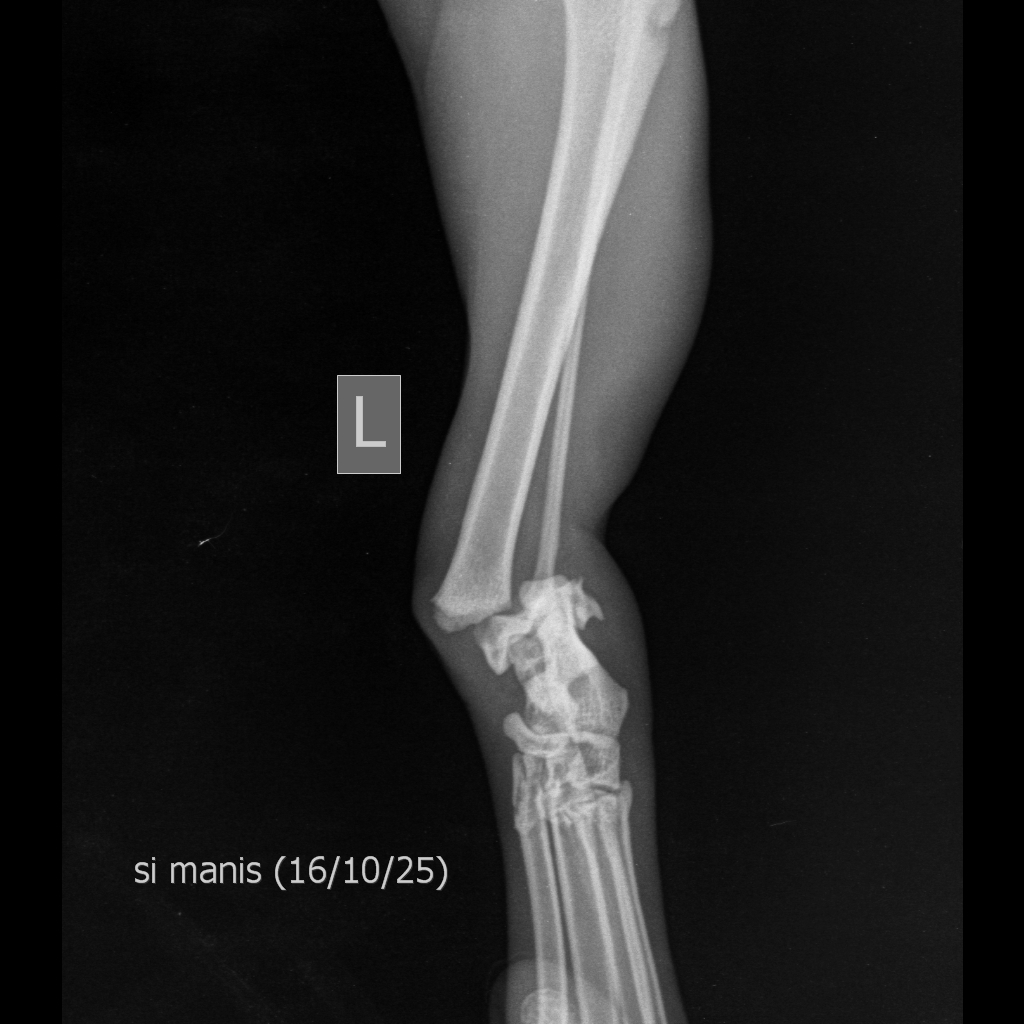

Si Manis kaki kirinya patah.

Si Manis X-ray patah kakinya.